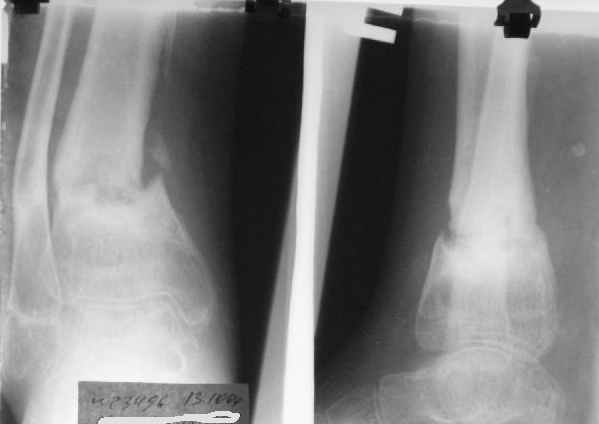

Перелом костей н\3 правой голени со смещением. Перелом большеберцовой кости можно охарактеризовать как компрессионно-оскольчатый.

Скелетное вытяжение за пяточную кость.

Формирование некроза кожи по задней поверхности н\3 голени~ 1 %, вторичное заживление, кожная пластика. Нейропатия м\берцового нерва (отсутствие активного разгибания 1 пальца) На вытяжении около 8 нед, в дальнейшем в гипсовых повязках ~ 8 мес.

В январе 2005: варусная деформация н\3 голени, болевой с-м, комбинированная контрактура г\стопного сустава, нейропатия м\берцового нерва сохраняется слабость разгибания 1 пальца.